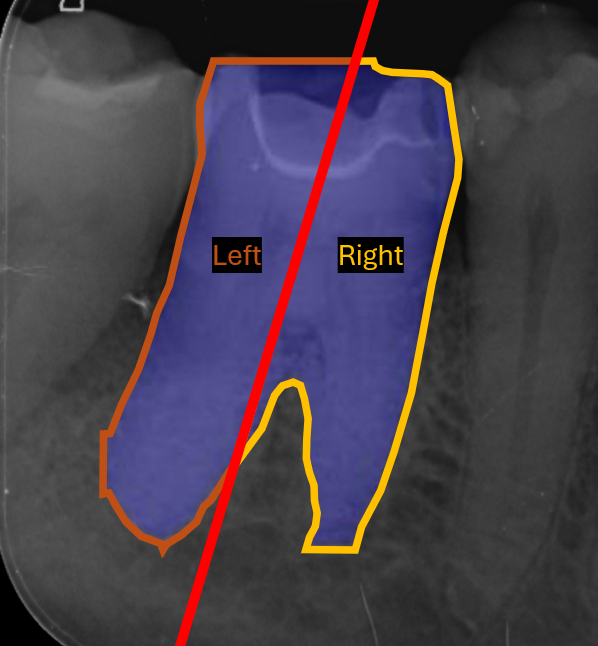

The initial stage of the post-processing module estimates the orientation of each tooth object from predicted tooth segmentation masks, in Figure 4(b). We first refine the predicted binary mask by retaining only the largest connected component, from which the boundary pixels are extracted using the Canny edge detector. Second order central moments [45] are then calculated from the edge representation of a tooth mask, where the principal axis of the tooth is then derived, giving us the orientation of the tooth mask normalised between 90-90^{\circ} and 9090^{\circ}. This tooth orientation acts as a rotation index for subsequent tooth alignment and for evaluation purposes.

Refer to caption

(a) Predicted Keypoints/Masks

(b) Tooth Orientation

(c) Mask Partitioning

(d) Edge Association

(e) Mask-Keypoint Matching

(f) Mesial/Distal Determination

Figure 4: Handmade example diagrams, with synthetic data, depicting each stage of the post-processing module overlaid on Image104.

Once the orientation is derived, each tooth mask is split into left and right halves, by constructing a rotated bisector through its centroid, in Figure 4(c). This step ensures that all subsequent anatomical assignments are performed relative to the true orientation of each tooth independently, rather than the image axes.

The post-processing module then determines the mask edge pixel associations for each predicted keypoint to the anatomical boundaries of each predicted tooth. The lowest Euclidean distance for a given keypoint to each closest edge pixel for all mask halves is chosen. This provides a geometric link between anatomical landmarks and boundary structures, allowing precise localisation relative to tooth edges. This step can be seen in Figure 4(d), where the red point is a single example of a predicted keypoint, the green point is the closest edge pixel for the closest segmentation mask halve, and yellow points are the closest edge pixel for all other mask halves.

To resolve which mask best corresponds to a given group of keypoints, the average distance between visible keypoints and their associated edges is computed. The mask with the smallest mean distance is selected as the most appropriate match, effectively filtering out false positive masks.

At this stage we have many keypoint-edge associations for all predicted keypoints, where each keypoint has an association for every predicted left and right side segmentation mask in the image. The post-processing module then proceeds to match each predicted keypoint group with its most likely associated predicted mask, by choosing the mask with the lowest average distance across all visible keypoints in the group. This process filters out false postive mask predictions, by disregarding non matched masks. This process can be seen in Figure 4(e), where green points are the closest edge pixel for a given predicted red keypoint, and yellow keypoints are the edge pixels for the matched segmentation mask if that keypoint’s closest edge pixel is not with the matched mask.

Finally, the post-processing module determines which sides of the image are mesial and distal. These are determined by distance based majority voting across visible keypoints for mesial and distal related keypoints. Each keypoint is assigned to the closest side of the matched mask, and votes are accumulated by anatomical keypoint class. The side with the most votes for mesial keypoints defines the mesial half, with the distal side assigned as its inverse. The final post-processed keypoints replace raw predictions when appropriate, ensuring consistent anatomical alignment across all teeth, as shown in Figure 4(f).